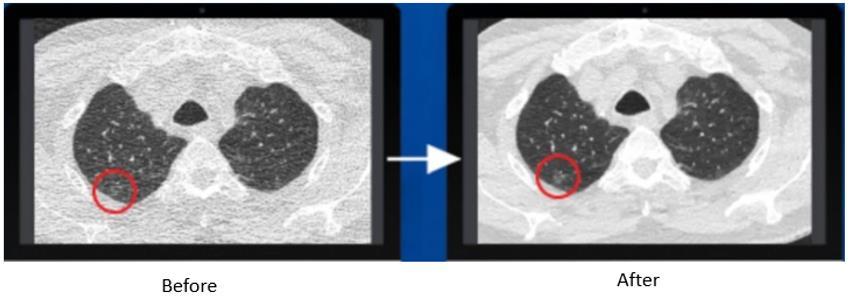

Convolutional Neural Networks (CNNs) play a significant role in CT imaging for overcoming the issue of low-dose CT optimization. Since radiation damage needs to be kept to a minimum, especially in children and patients requiring more thanoneortwoscans,low-doseCTscansare,however,invariablynoisyandlow-qualityimages-infact,suchpoor-quality images are unlikely to provide any meaningful diagnosis. In direct contrast, CNNs have tackled this problem with great success by learning mappings from low to high doses, or effectively reconstructing good-quality high-dose scans even while exposing patients to minimal radiation. The mapping was performed through successive convolutional layers that instinctively learn to detect and accentuate relevant structures such as bones, blood vessels, and tumors. Because prominent features thus remain salient in imaging for which reconnaissance is possible, CNNs enable a high-quality diagnosiswithoutcompromisingpatientsafety.

MetalartifactreductionisanotherimportantapplicationofCNNinCTimaging.Metalimplantssuchasdentalfillingsand hipreplacementsoftencauseveryseverestreakartifactsintheCTimages,preventing propervisualizationofthetissues surroundingtheseartifacts.CNNsaretrainedtorecognizeandreducethesedistortions,resultinginimprovedqualityfor these images to allow for better interpretation. The networks are trained using pairs of images, low-quality images that are affected by metal artifacts, and high-quality images without these effects, to differentiate genuine anatomical structures from artifacts. Thus, radiologists are expected to enjoy clearer visuals with their decisions in even more challengingsituationsinvolvingmetal-induceddistortions.

Generative Adversarial Networks (GANs) signify a massive change in CT imaging, especially by denoising low-dose CT scans and enhancing image quality. As CT imaging relies on X-rays, in an attempt to lower the dose, one increases noise that outweighs fine details and limits diagnosis. GANs will generate high-quality images from noisy low-dose inputs. A generator produces synthetic images resembling high-dose scans while the discriminator studies these outputs by enforcing the trained discriminator to consider these from a high-quality reference. The iterative process of eradicating noise from standard-dose CT scans upholds diagnostic integrity. This is especially important in oncology because a clear visualizationoftumoredgeswillleadtotherighttreatmentdecisions.

Another area of great merit of GANs lies in image fusion and the reconstruction thereof. In situations with multimodal imaging, as would be PET-CT, which requires both anatomical and functional information to be visible, here GANs allow data from different modalities to be fused into thecreation of a unified high-quality image. This fusion enhances their visibilityofcomplexconditions;thus,radiologistscanseeboththestructuralandmetabolicaspectsofaparticulardisease froma singleimage. ThegistisgivenbyGANssincetheycanrealignandcombinedetailsfrom PETandCTscanstogive informationcrucialforeachdiagnosisandpersonalizedtreatmentplanning.

Figure 5: CT scans before and after AI enhancement, illustrating noise reduction, motion artifact correction, and improved resolution.